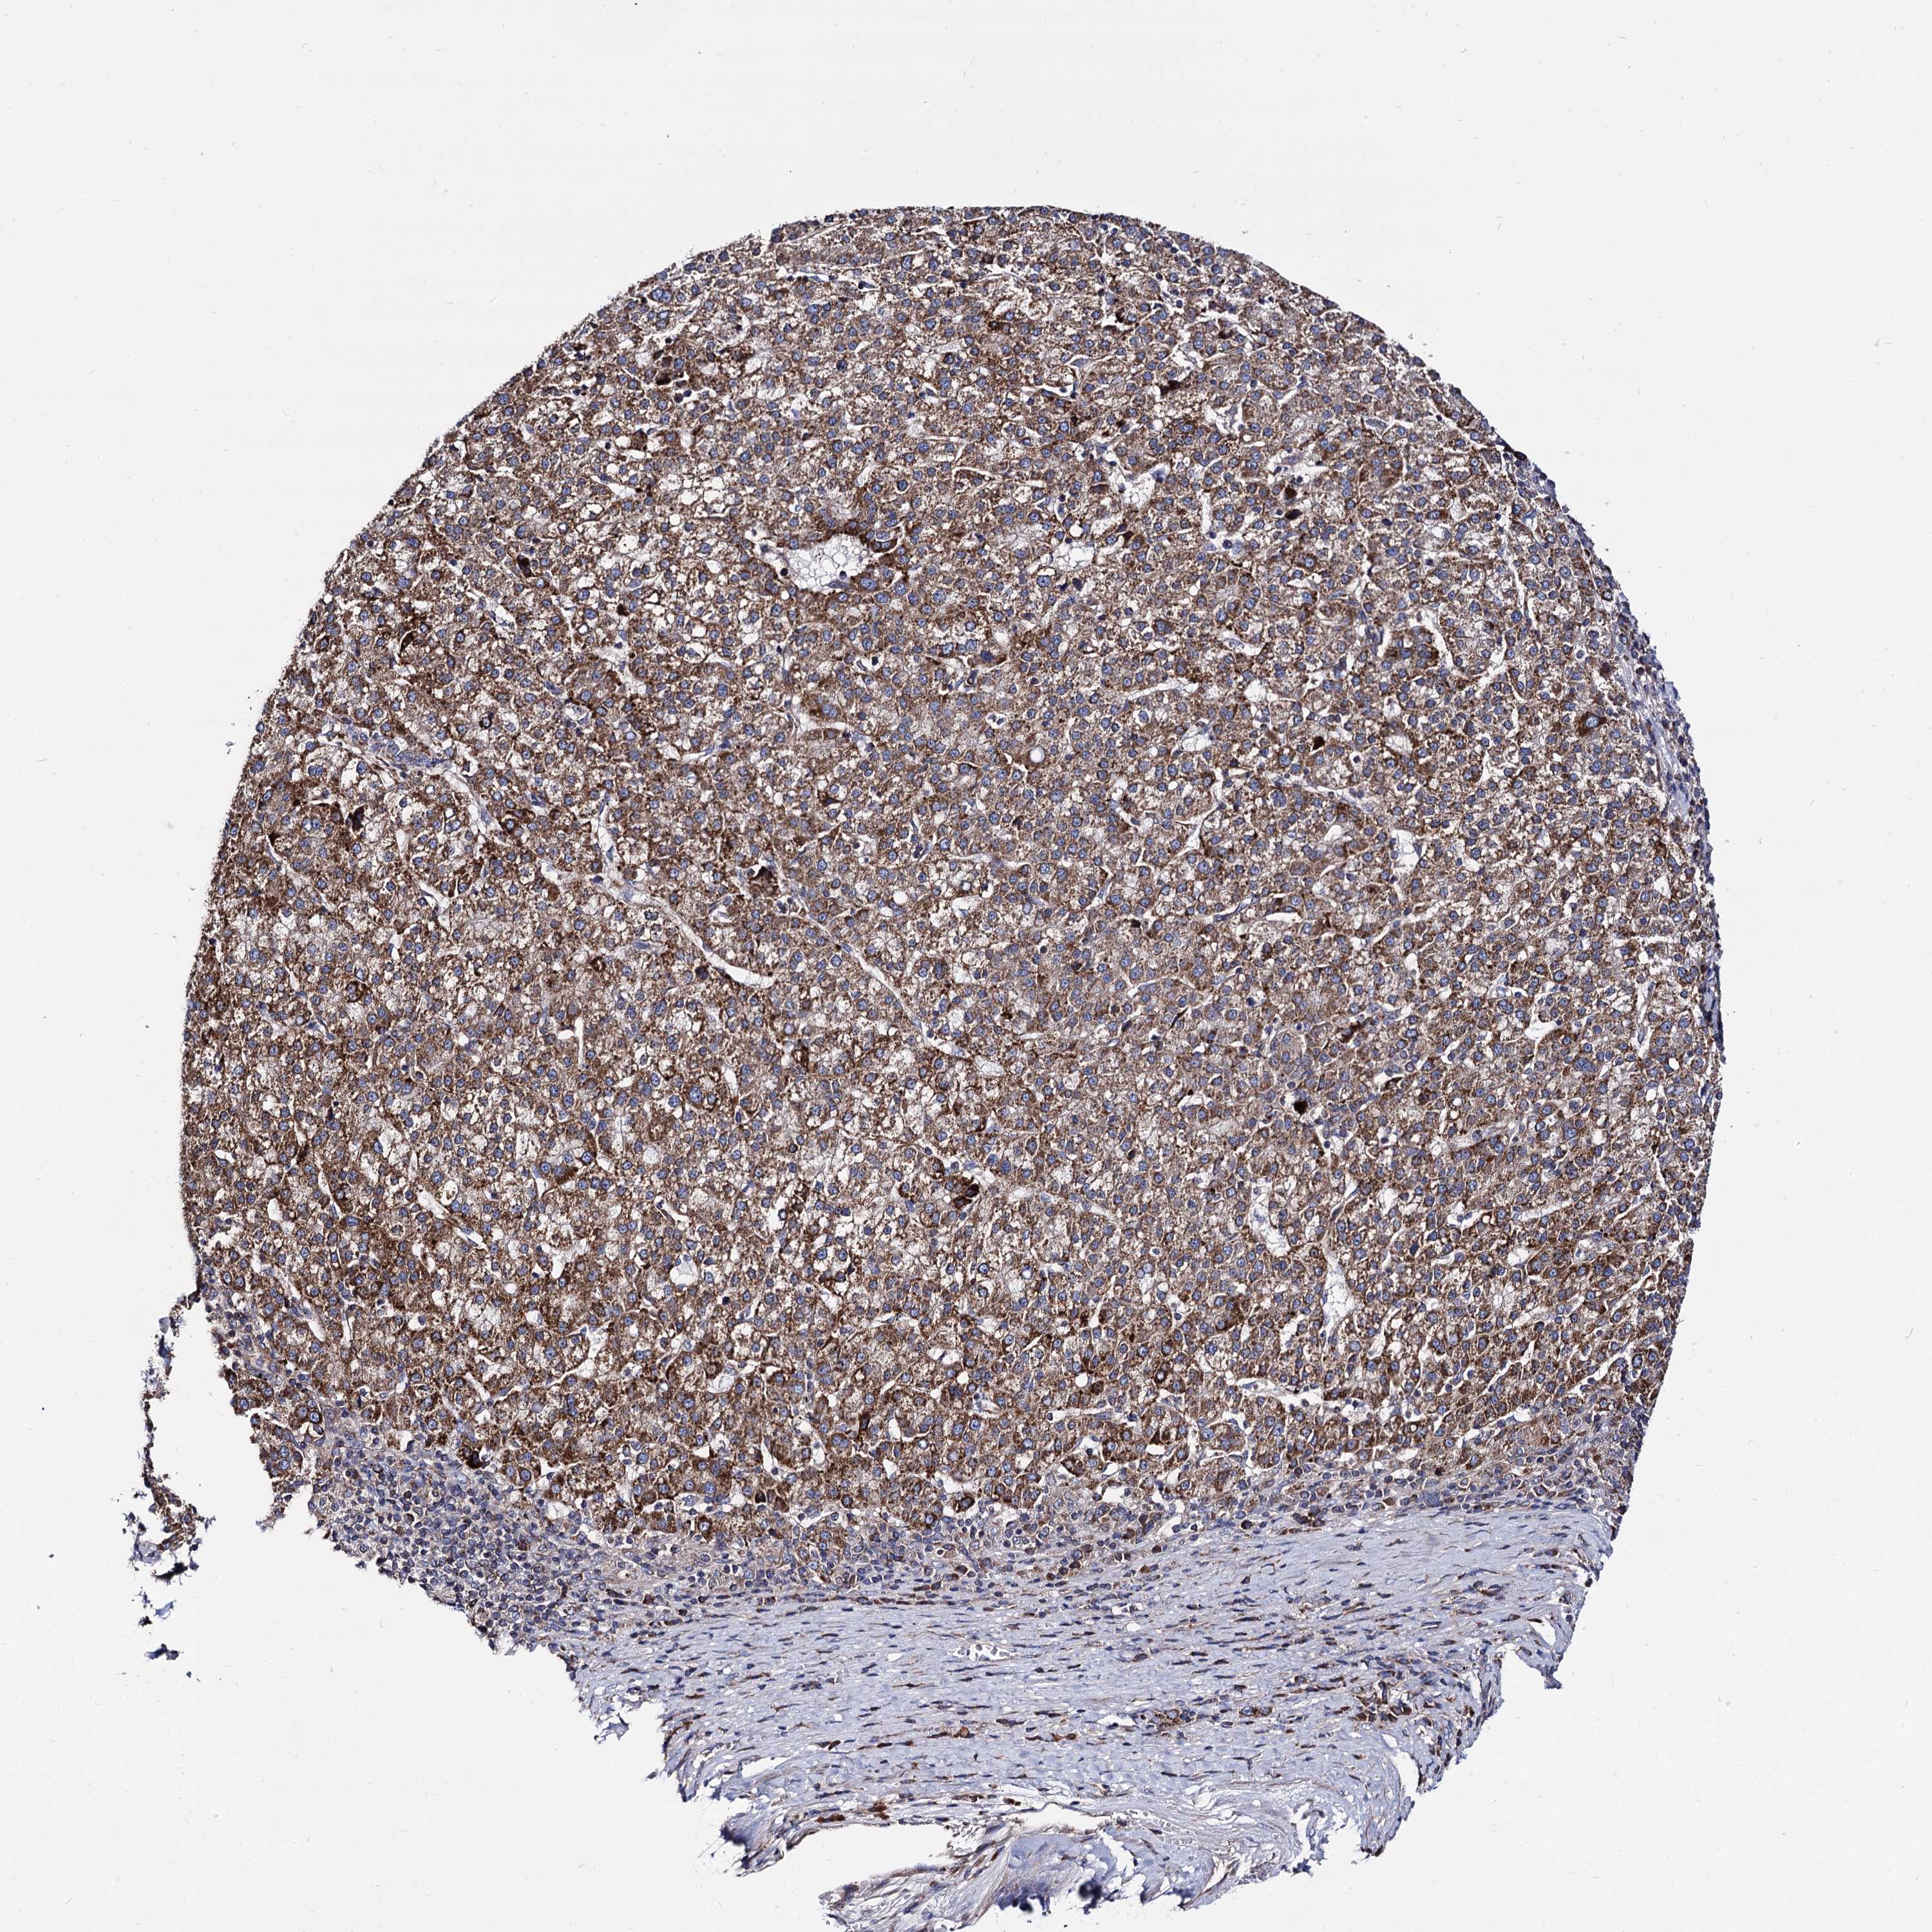

LIVER CANCER - Protein expressioni

A mouse-over function shows sample information and annotation data. Click on an image to view it in a full screen mode. Samples can be filtered based on level of antibody staining by selecting one or several of the following categories: high, medium, low and not detected. The assay and annotation is described here.

Note that samples used for immunohistochemistry by the Human Protein Atlas do not correspond to samples in the TCGA dataset.

Antibody stainingi

Antibody staining in the annotated cell types in the current human tissue is reported as not detected, low, medium, or high, based on conventional immunohistochemistry profiling in selected tissues. This score is based on the combination of the staining intensity and fraction of stained cells.

Each image is clickable and will lead to virtual microscopy that enables deeper exploration of all samples and also displays staining intensity scores, fraction scores and subcellular localization as well as patient and tissue information for each sample.

Antibody HPA040845

Staining

High

Medium

Low

Not detected

Intensity

Strong

Moderate

Weak

Negative

Quantity

>75%

75%-25%

<25%

None

Location

Nuclear

Cytoplasmic/membranous

Cytoplasmic/membranous,nuclear

Cholangiocarcinoma

Carcinoma, Hepatocellular, NOS